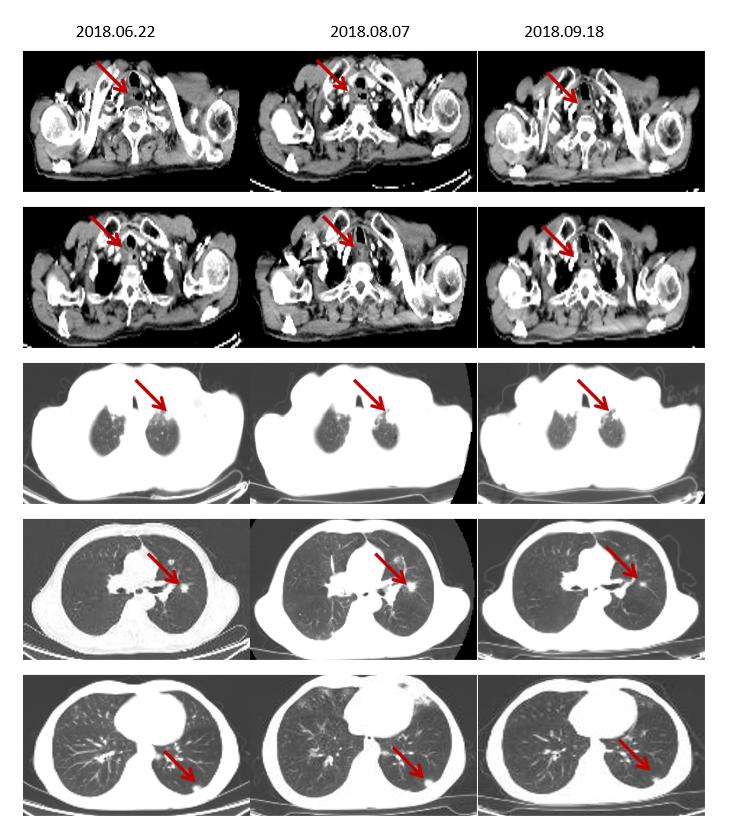

2018.06入院复查疾病进展(食管上段占位,较前相仿;双肺多发结节,较前增大、增多,考虑转移),病理补做免疫组化:PDL-1 (5%弱+)。筛选入组“在一线治疗失败的晚期/转移性食管鳞癌受试者中比较IBI308与紫杉醇或伊立替康治疗有效性和安全性的随机、开放、多中心、II期研究(ORIENT-2)”的临床试验。入IBI308组,于2018.06.27、2018-7-17、2018-08-09、2018-8-31、2018-9-20、2018-10-11、2018-11-01、 2018-11-22、 2018-12-13、2019-01-03、2019-01-22给予“IBI308”治疗13周期。

2周期复查(2018.08.07)部分肺转移灶较前稍增大(假性进展),4周期及以后食管壁增厚较前好转,肺转移灶较前缩小,临床疗效PR。